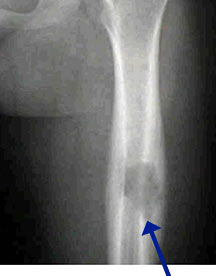

- May arise from any bone and any site within a bone (epiphyseal, metaphyseal, diaphyseal)

- Radiographically variable appearance: may appear benign (geographic) or malignant (permeative or moth eaten)

Sites:

- Flat Bones (most common—70%)

- Femur

- Humerus